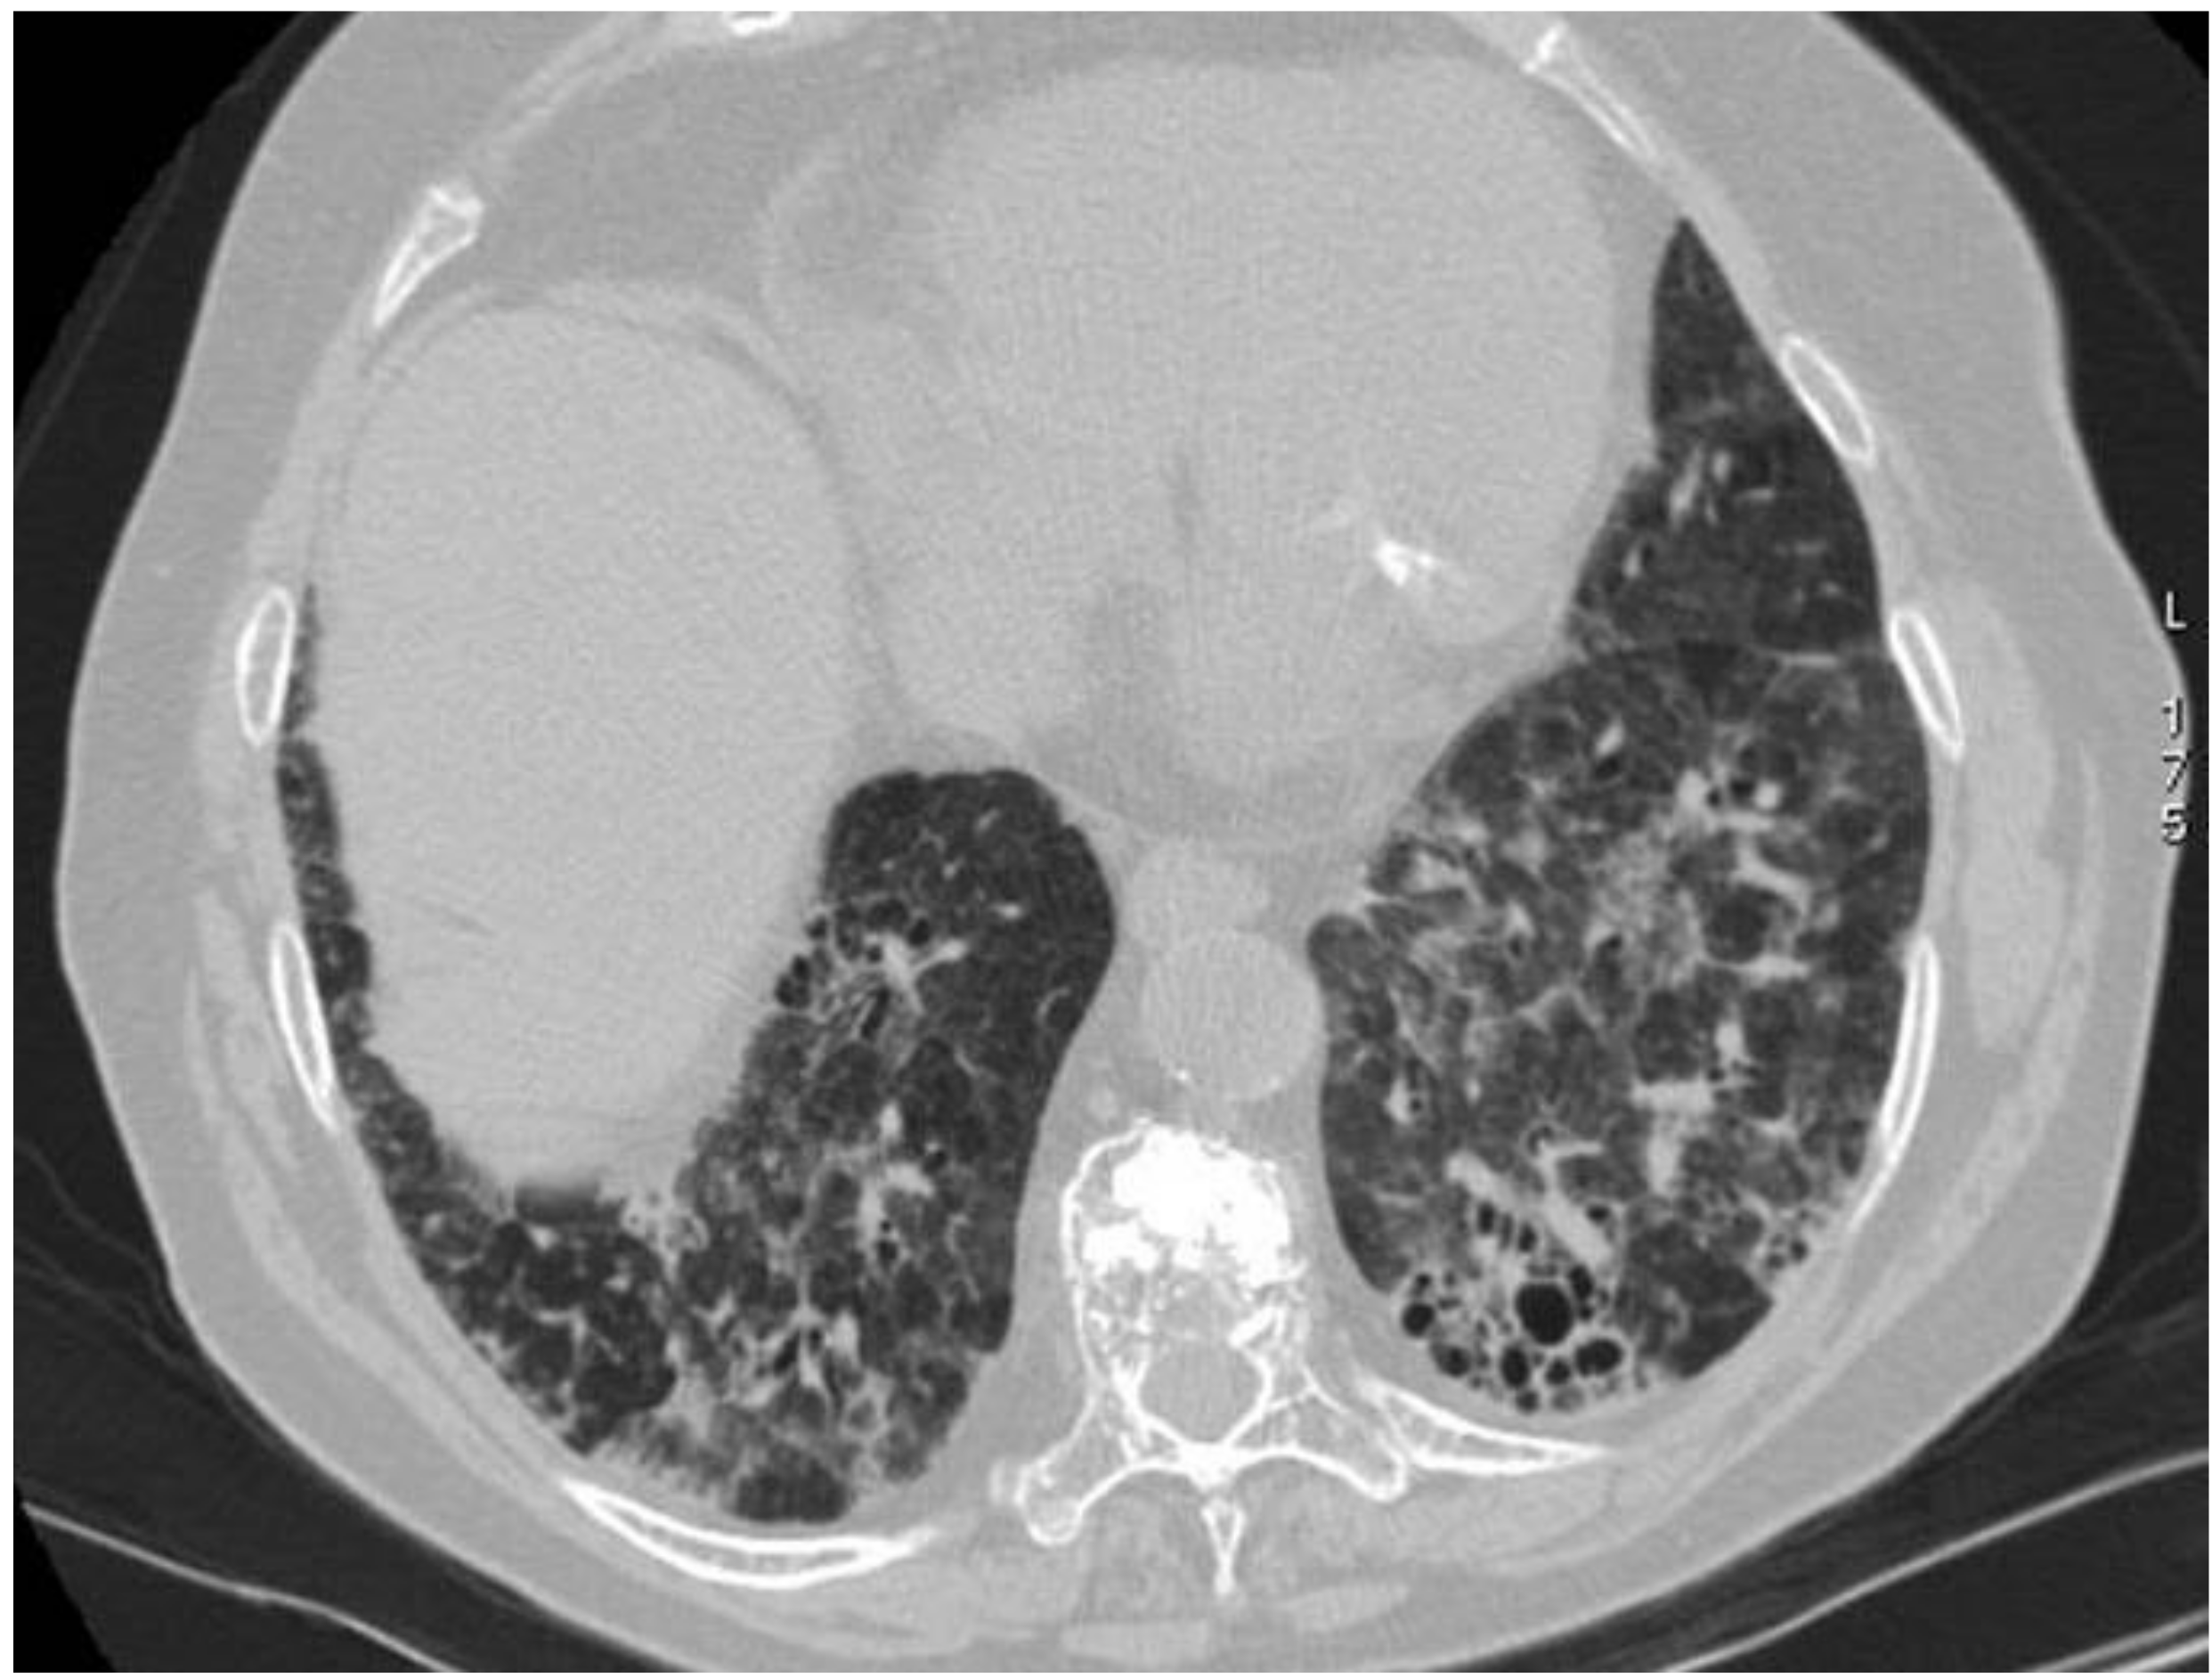

2.5. Eosinophilic Granulomatosis with Polyangiitis (EGPA-Churg-Strauss)

| EGPA | Migrant GGOs, transient consolidation, irregular bronchial wall thickening, small nodules with peribronchial and centrilobular distribution, pleural effusion. |